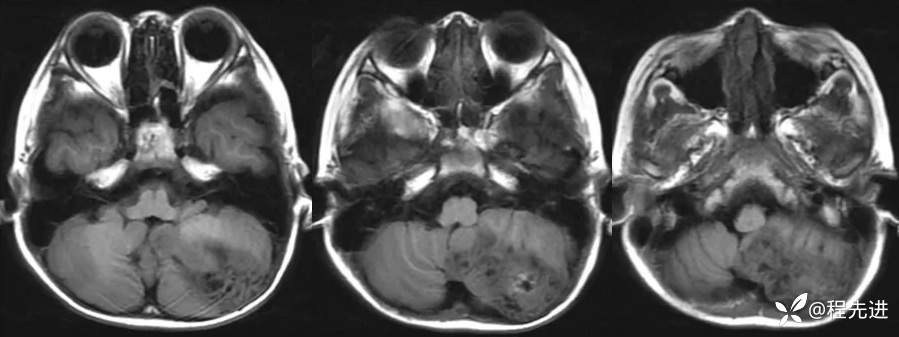

【患者信息】:男,6岁

【主诉】:查体发现左侧小脑半球占位3个月

【现病史及既往史】:患者3个月前因鼻塞至外院就诊,行头颅CT检查偶然发现颅内占位

【检查】